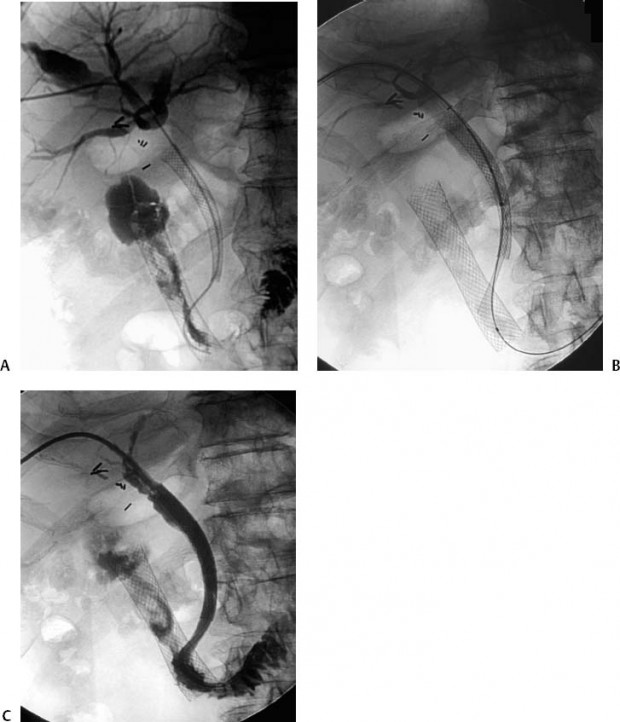

From radiologykey.com

63 Nephrostomy Catheter Placement Radiology Key Is A Nephrostomy Tube A Urinary Catheter The tube helps to drain urine from your body. A urostomy is an abdominal wall opening that allows urine to leave the body through a stoma. The drained urine is collected in a small bag located. this information is about putting a small tube called a nephrostomy catheter through the skin into your kidney to drain urine (pee). A. Is A Nephrostomy Tube A Urinary Catheter.

From www.jvir.org

A Durable Percutaneous UTube Nephrostomy for Management of a Is A Nephrostomy Tube A Urinary Catheter A urostomy is an abdominal wall opening that allows urine to leave the body through a stoma. A thin, flexible tube goes. The drained urine is collected in a small bag located. a nephrostomy is a tube that lets urine drain from the kidney through an opening in the skin on the back. this information is about putting. Is A Nephrostomy Tube A Urinary Catheter.